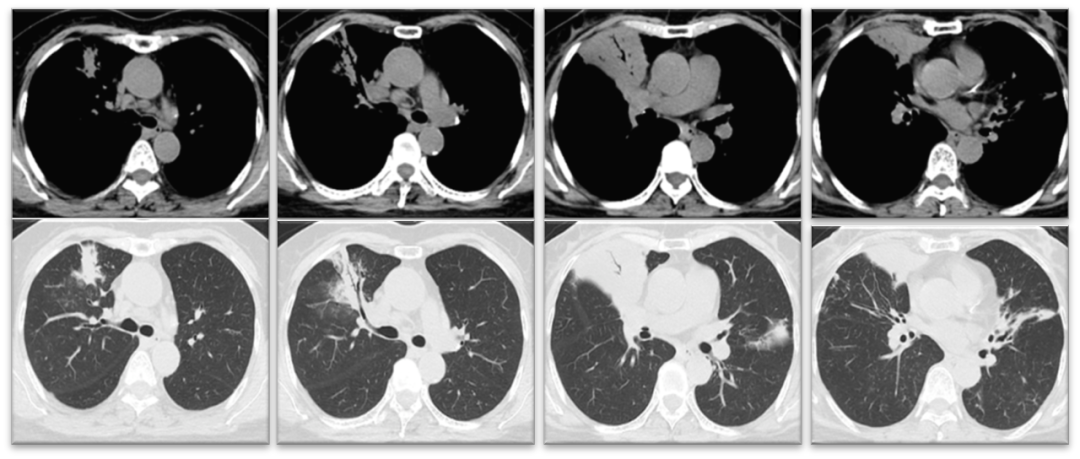

复查胸部CT平扫(2022年3月3日):右中肺叶、左肺舌叶及两肺下叶支气管扩张伴感染;均较前相仿(图2)

图2  右中肺及左肺舌叶、两肺下叶支气管扩张伴感染,较前相仿